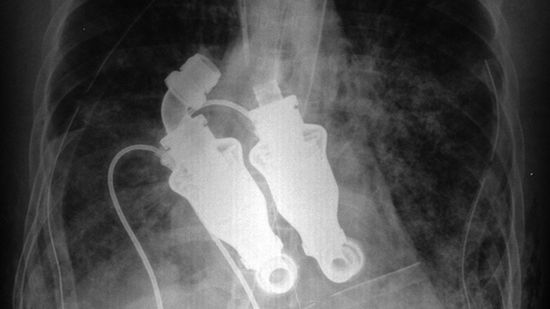

Wszystko dzięki turbinom, które zastąpią ludzkie serce. Jeden ze sprawdzonych sposobów na stwierdzenie, czy ktoś jest martwy, przechodzi powoli do historii. Osoba, której wszczepiono urządzenie widoczne na fotografii, nie będzie miała pulsu.

Sztuczne serce złożone z turbin zostało skonstruowane w Texas Heart Institute. Na razie nie otrzymało jeszcze certyfikatu FDA, ale przeprowadzono już udane próby na zwierzętach. Sukcesem zakończyła się również operacja wszczepienia turbin człowiekowi i jak dotąd nie odnotowano negatywnych skutków ubocznych.

Większość sztucznych serc, które powstały do tej pory, naśladuje działanie naturalnego organu. Tymczasem ten sam efekt da się uzyskać w wydajniejszy sposób przy zastosowaniu turbin. Według konstruktorów są one mniej awaryjne, prostsze w konstrukcji oraz wydajniejsze.

Jeżeli wszystkie zapewnienia konstruktorów okażą się prawdziwe, to brak pulsu i płaskie EKG będą akceptowalną ceną za takie sztuczne serce.